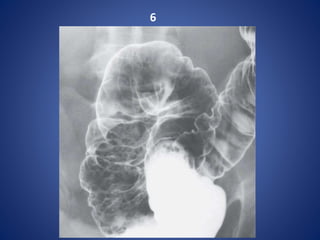

6

Numerous punctate collections of barium surrounded by

radiolucent halos --- represents Aphthoid ulcers.

CROHN COLITIS